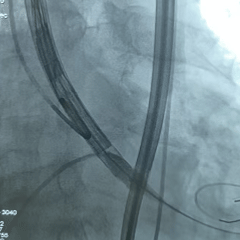

手术过程

左侧冠脉造影

右侧冠脉造影并行PCI

根部造影

可见瓣叶钙化,伴反流

TF21瓣膜0位初始释放

全展开后多角度根部造影:瓣膜深度形态合适,冠脉灌注良好,少量瓣周漏,选择解锁脱钩

脱钩后造影评估:瓣膜深度可,展开良好,少量瓣周漏

外周造影检查,血管无损伤